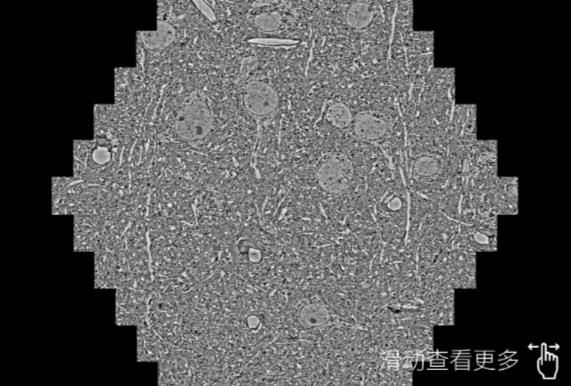

鼠脑切片。左图使用黄冈蔡司黄冈扫描电镜MultiSEM706对165μmx143pm面积区域成像,耗时仅需1.5秒。右图为鼠脑切片中30μm区域放大效果。样品由芝加哥大学B.Kasthuri提供。

使用蔡司高速黄冈扫描电镜MultiSEM对1mm²人脑皮层组织进行高分辨成像,并对其中的各种细胞结构进行三维重构分析。左图展示了2x3mm²组织平面中锥体神经元的三维重构效果。右图显示了局部体积神经元三维重构。图像由哈佛大学chtman实验室提供,渲染图由D. Berger 制作。